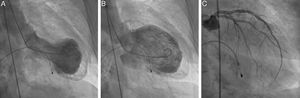

A transthoracic echocardiogram revealed severe left ventricular (LV) systolic dysfunction with akinesia of the mid-apical segments and hyperkinesis of the basal segments. Assuming a possible previous infarction with post-infarction angina and severe conduction abnormalities, cardiac catheterization was performed and temporary transvenous pacing was instituted. The coronary angiography excluded significant coronary vascular disease: 40% stenosis of the mild left anterior descending artery (LAD) and 50% of the distal circumflex coronary artery (Figure 2). The left ventriculography demonstrated typical “apical ballooning” and an apical thrombus (Figure 2, video 1). Contrast echocardiography confirmed the presence of apical thrombus and hypocoagulation therapy was initiated (Figure 3).

Results of cardiac catheterization. Left ventriculography at end-systole (A) and end-diastole (B) demonstrating typical apical ballooning and double outline apex suggestive of apical thrombus. Results of selective coronary angiography of the left main coronary artery (C) showing no significant stenosis.